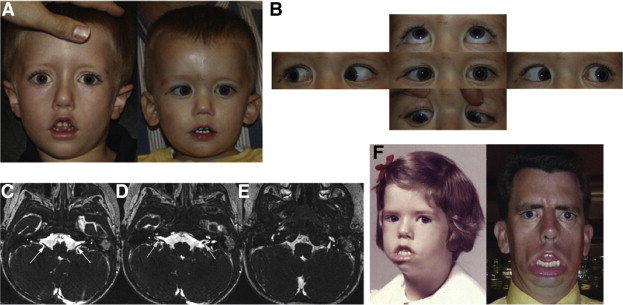

- hoxa1 geni ve bosley-salih-alorainy sendromu: genellikle suudi arabistan ve türk asıllı bireylerde görülen bir sorundur. nörogörüntülemelerde tipik olarak tanımlanamayan nervus abducens ve anormal iç kulak anatomisi rapor edilmiştir. iç karotis arter malformasyonları tek taraflı hipoplaziden bilateral ageneze kadar değişiklik gösterebilir.